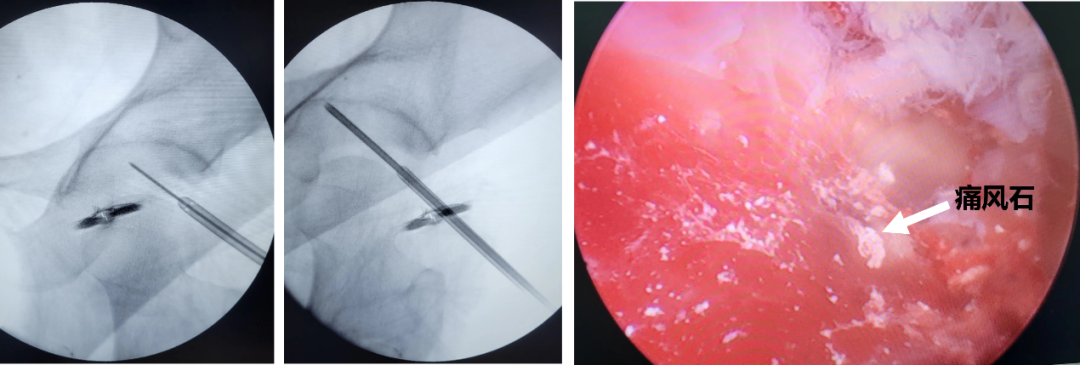

近日,患者小陈因酒后突发左侧髋部剧痛、不能活动,急诊入我院骨科“入院时简直生不如死,关节不敢伸直,甚至不敢做任何活动,特别影响睡觉和休息”,小陈痛苦回忆到。经检查,我院骨科诊断为“左侧髋关节痛风性关节炎急性发作”。主管医生丁虹表示:患者为青年男性,既往有高尿酸血症病史,未规范治疗和严格控制饮食,结合患者症状体征及检查结果,痛风性关节炎诊断明确,但像小陈这样重的症状,并不多见。明确诊断后,对患者进行了正规保守治疗,尿酸值降至正常,疼痛症状好转,但活动恢复仍不理想,骨科曹治东主任考虑与关节通风结晶及炎症因子沉积有关,决定予以髋关节镜下探查、清理、关节囊切开减压术,术后患者疼痛症状进一步缓解,左侧髋关节活动完全恢复。“终于可以睡个安稳觉啦!”小陈一脸惊喜。

图片 术中透视及髋关节镜下痛风石结晶

骨科曹治东主任表示:对于痛风性关节炎目前主张保守联合微创手术治疗,但髋关节镜微创手术目前能成功开展的医院较少,大部分仍采用切开手术,创伤大不说,还容易导致股骨头坏死。我们自2018年成功开展第一例髋关节镜以来,已成功开展多例类似手术,均取得较好效果。